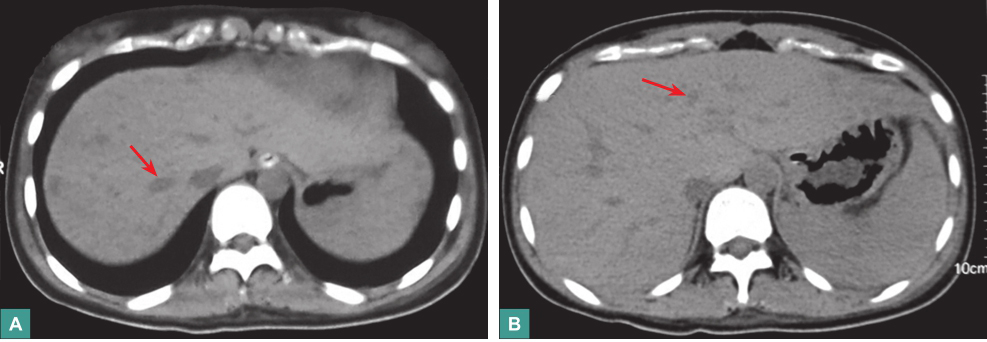

(3)腹部CT平扫

肝实质见多发低密度影,少量腹腔积液,脾大(图2)。

图2腹部CT表现

4.影像学检查

胸部X线片未见双肺感染性病变,心影正常。腹部CT可见肝内多发低密度灶,腹腔少量积液,脾大。

患者近期有重症病毒性心肌炎、心源性休克、急性肾损伤病史,目前主要症状为上腹部疼痛及压痛、黑便,腹部CT平扫见肝脏多发低密度灶,提示病变位于上消化道和肝脏。

本例患者出现发热,PCT、白细胞计数明显升高,腹部CT平扫示肝实质内多发低密度灶,SOFA评分>2分,脓毒症的诊断成立,肝脏病变首先考虑为感染所致。患者近期有休克、消化道黏膜屏障缺血损伤以及大剂量使用激素等情况,易导致肠道细菌移位,肝脏病灶首先考虑为胃肠道细菌移位导致的迁徙性肝脓肿,需血培养、腹部增强CT扫描等协助诊断,必要时可考虑行局部病灶活检明确诊断。